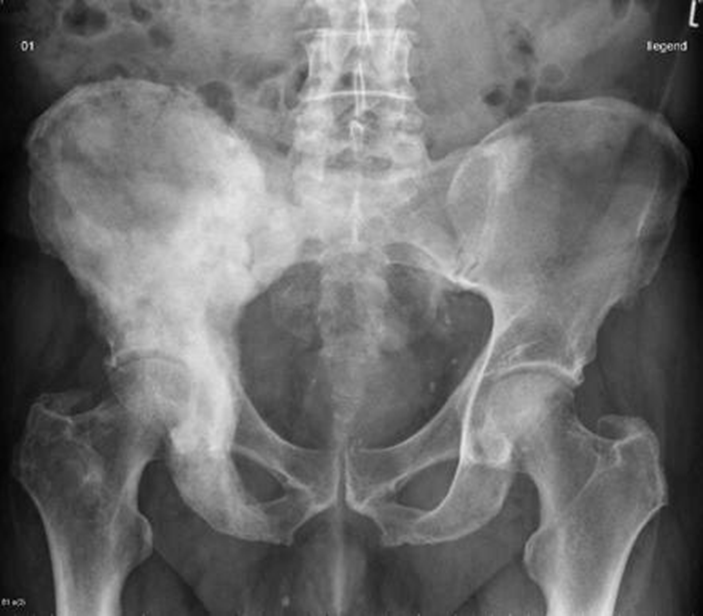

65 year old with h/o prostate cancer complains of hip pain.

What is Paget's disease?